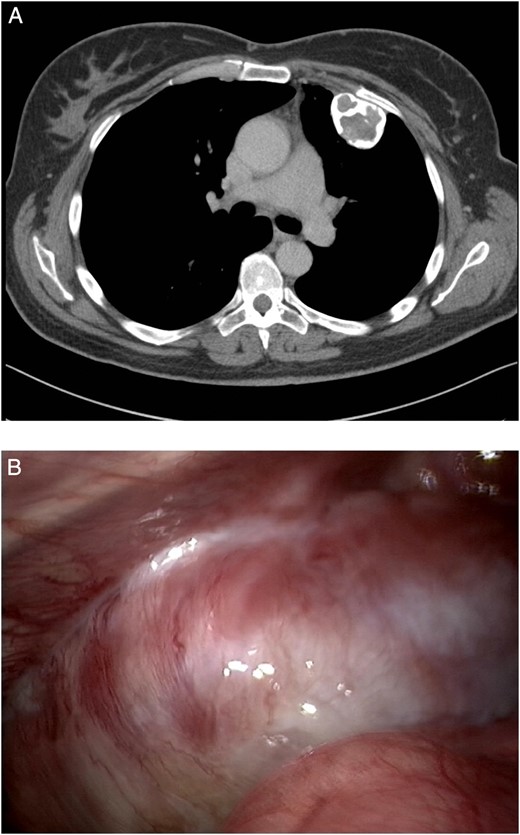

With no other lesions explaining the chronic cough, resection through video-assisted thoracoscopy (VATS) was planned in multidisciplinary consultation. During VATS, a bony tumour was found originating from the left second and third rib, with some pleural adhesions (Fig. 1B). The procedure was converted to thoracotomy to perform wide resection of the thoracic wall (Fig. 2).

(A) Conversion to thoracotomy. (B) Chest wall defect after resection of the tumour.

The size of the thoracic wall defect following resection measured 8 by 5.5 cm A patch was prepared using two polypropylene meshes and interpolate of methyl methacrylate (Fig. 3). The patch was placed and tightened to the periosteum using prolene sutures (Fig. 4). Figure 5 shows the resected tumour. Finally, subcutaneous tissue and skin were closed in layers using a Vicryl and intracutaneous Monocryl suture.